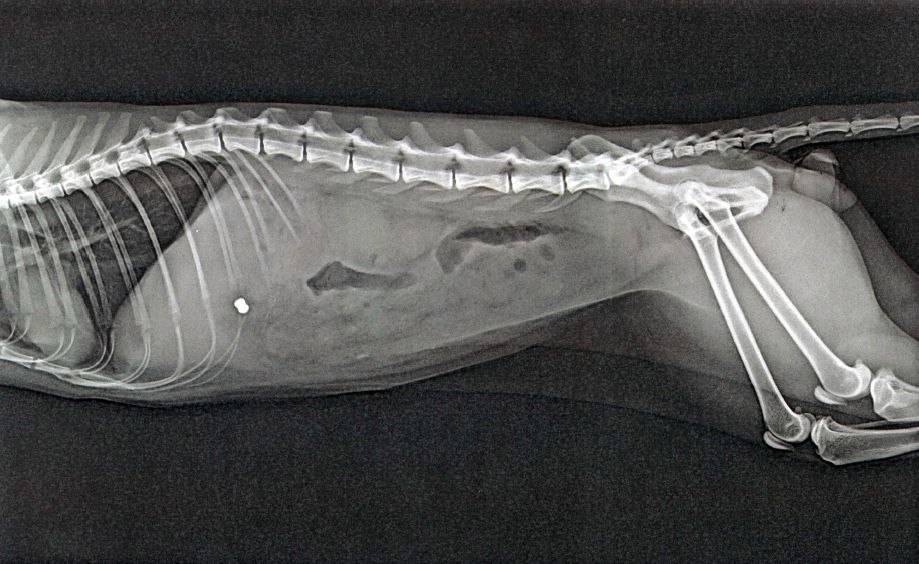

Sofort nach Entdeckung der Verletzung brachte die Katzenbesitzerin den Kater zum Tierarzt. Dort wurde das Tier geröntgt. Die Aufnahmen brachten dann die Diagnose: Der Kater wurde wohl mittels Luftdruckwaffe beschossen, denn deutlich war auf den Röntgenbildern ein so genanntes Diabolo-Projektil zu erkennen, welches an höchst lebensbedrohlicher Stelle in den Körper des Tieres eingedrungen war. Der Kater musste daraufhin eingeschläfert werden, da es keine Heilungschancen gab.

Das Bild zeigt die Verletzung des Katers. (externes Bild)